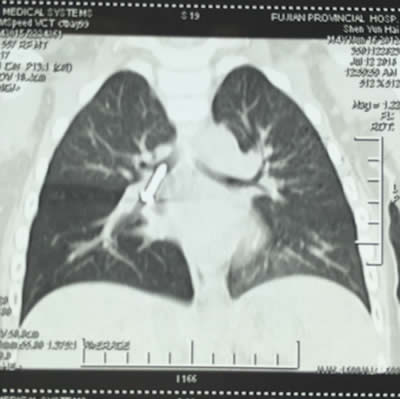

螺丝钉卡在宝宝气管 CT显示螺丝钉卡在右主支气管

参与手术的陈国郝副主任医师说,螺丝钉呛入气管不到1天,孩子已经出现了肺气肿,肺炎,所以手术越早越好。

手术医生把纤细的气管镜,深入宝宝喉部,看到右侧支气管中段有一金属的螺丝钉,尖端朝上,头端朝下。螺丝钉周围已经有脓性分泌物。在大家的配合下,仅5分钟,就顺利夹出了螺丝钉。螺丝钉足足有2.5厘米长,0.4厘米宽。